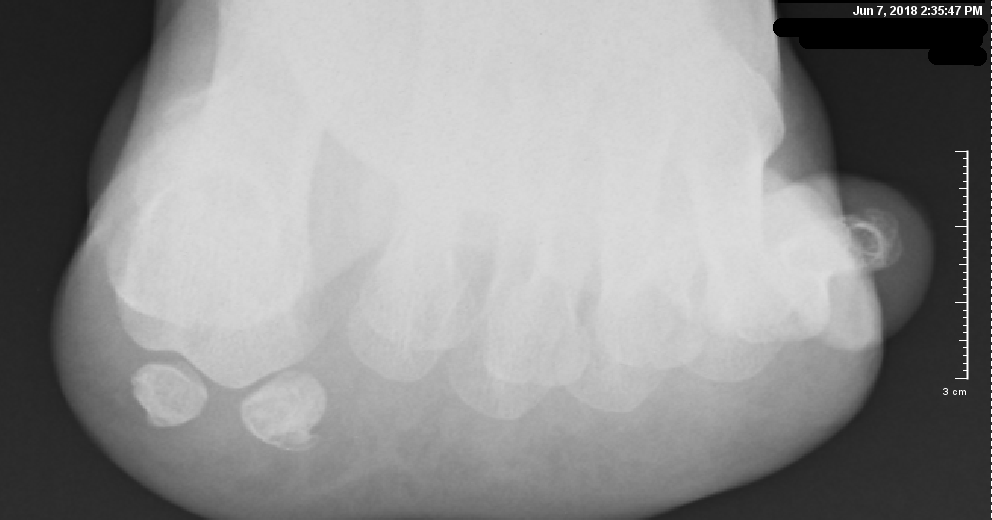

Acta scientific orthopaedics 3.3 (2020). Sesamoid fractures most commonly refer to the bones located under the big toe. Sesamoid bones are found embedded in the tendons near many joints.

Fracture usually found on xray.

Rest, ice, and elevate your foot. Turf toe is a hyperextension of the big toe joint in an upward direction. These foot bones are located underneath the foot, one on the outer side of the foot and the other near the middle of the the sesamoid bones are subject to breakage (fracture) as well as sesamoiditis. Sesamoid fracture and injuries treated by top foot surgeons in baltimore. Fracture of the medial sesamoid with slight edema (white arrow). Sesamoid fractures occur as a result of trauma to a previous unipartite sesamoid bone. 301 moved permanently these pictures of this page are about:sesamoid bone foot fracture. What is a sesamoid fracture? Often sesamoid fractures are described as turf toe. Sesamoid partition is a common normal variant. Sesamoiditis occurs on the bottom of the foot, just behind the big toe. Stress fractures of the sesamoid bones can also cause sesamoiditis. There are normally two sesamoid bones on each foot; The sesamoids are two bones underneath the great toe. These are the least common fractures of the forefoot. Four weeks ago i dropped a heavy object on my right foot. Although sesamoiditis used to be a rare cause of foot pain and disability, it has become more common in recent years, and it is.